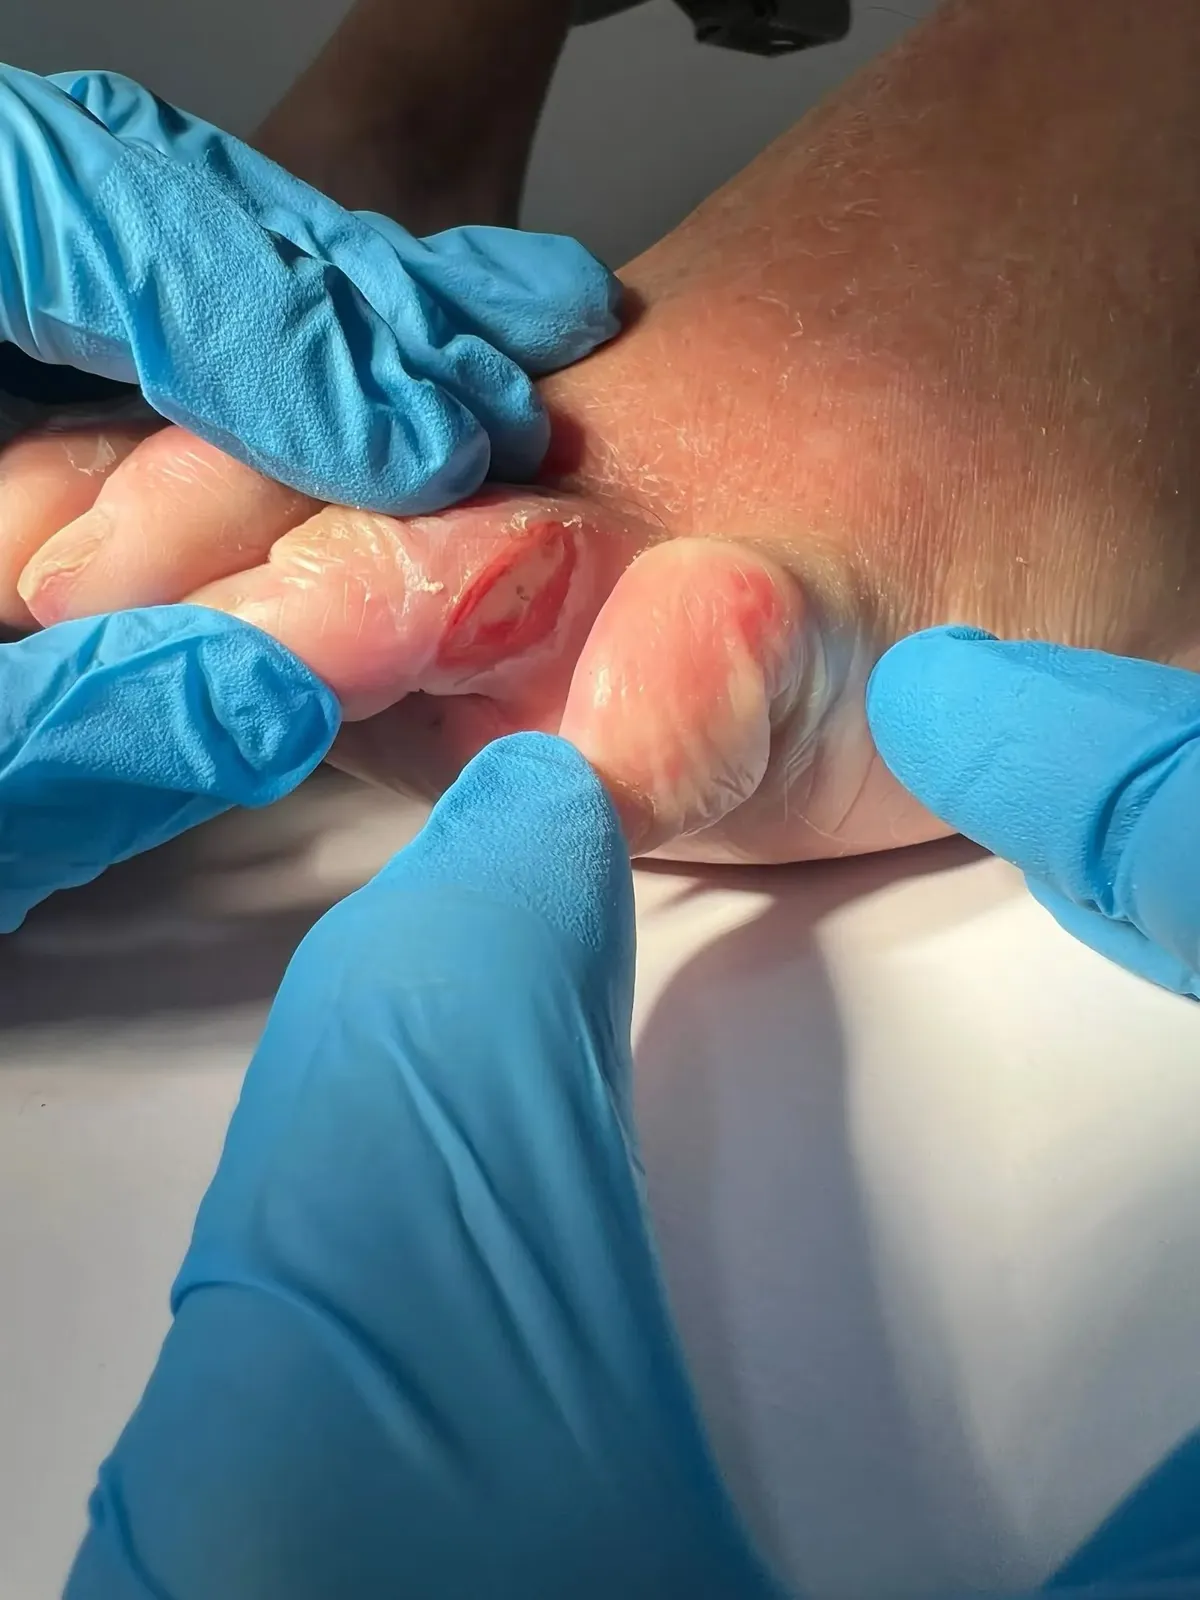

Figura 2: Aspecto clínico inicial. Observa la hiperqueratosis plantar bien delimitada en la zona metatarsal.

Lo que hacía este caso especialmente desafiante era la presentación bilateral: el pie derecho estaba afectado en la zona metatarsal central, mientras que el pie izquierdo presentaba la lesión en la zona del quinto metatarsiano.

Figura 3: Vista detallada de la lesión. El núcleo hiperqueratósico profundo es característico de la IPK.

- Lesiones bien delimitadas con núcleo hiperqueratósico profundo

- Dolor marcado a la presión directa y durante la carga

- Aspecto clínico inicial: Hiperqueratosis plantar metatarsal pie derecho

- Detalle de lesión: Núcleo hiperqueratósico profundo característico de IPK

- Vista clínica detallada: Lesión hiperqueratósica causante del dolor tipo “clavo”